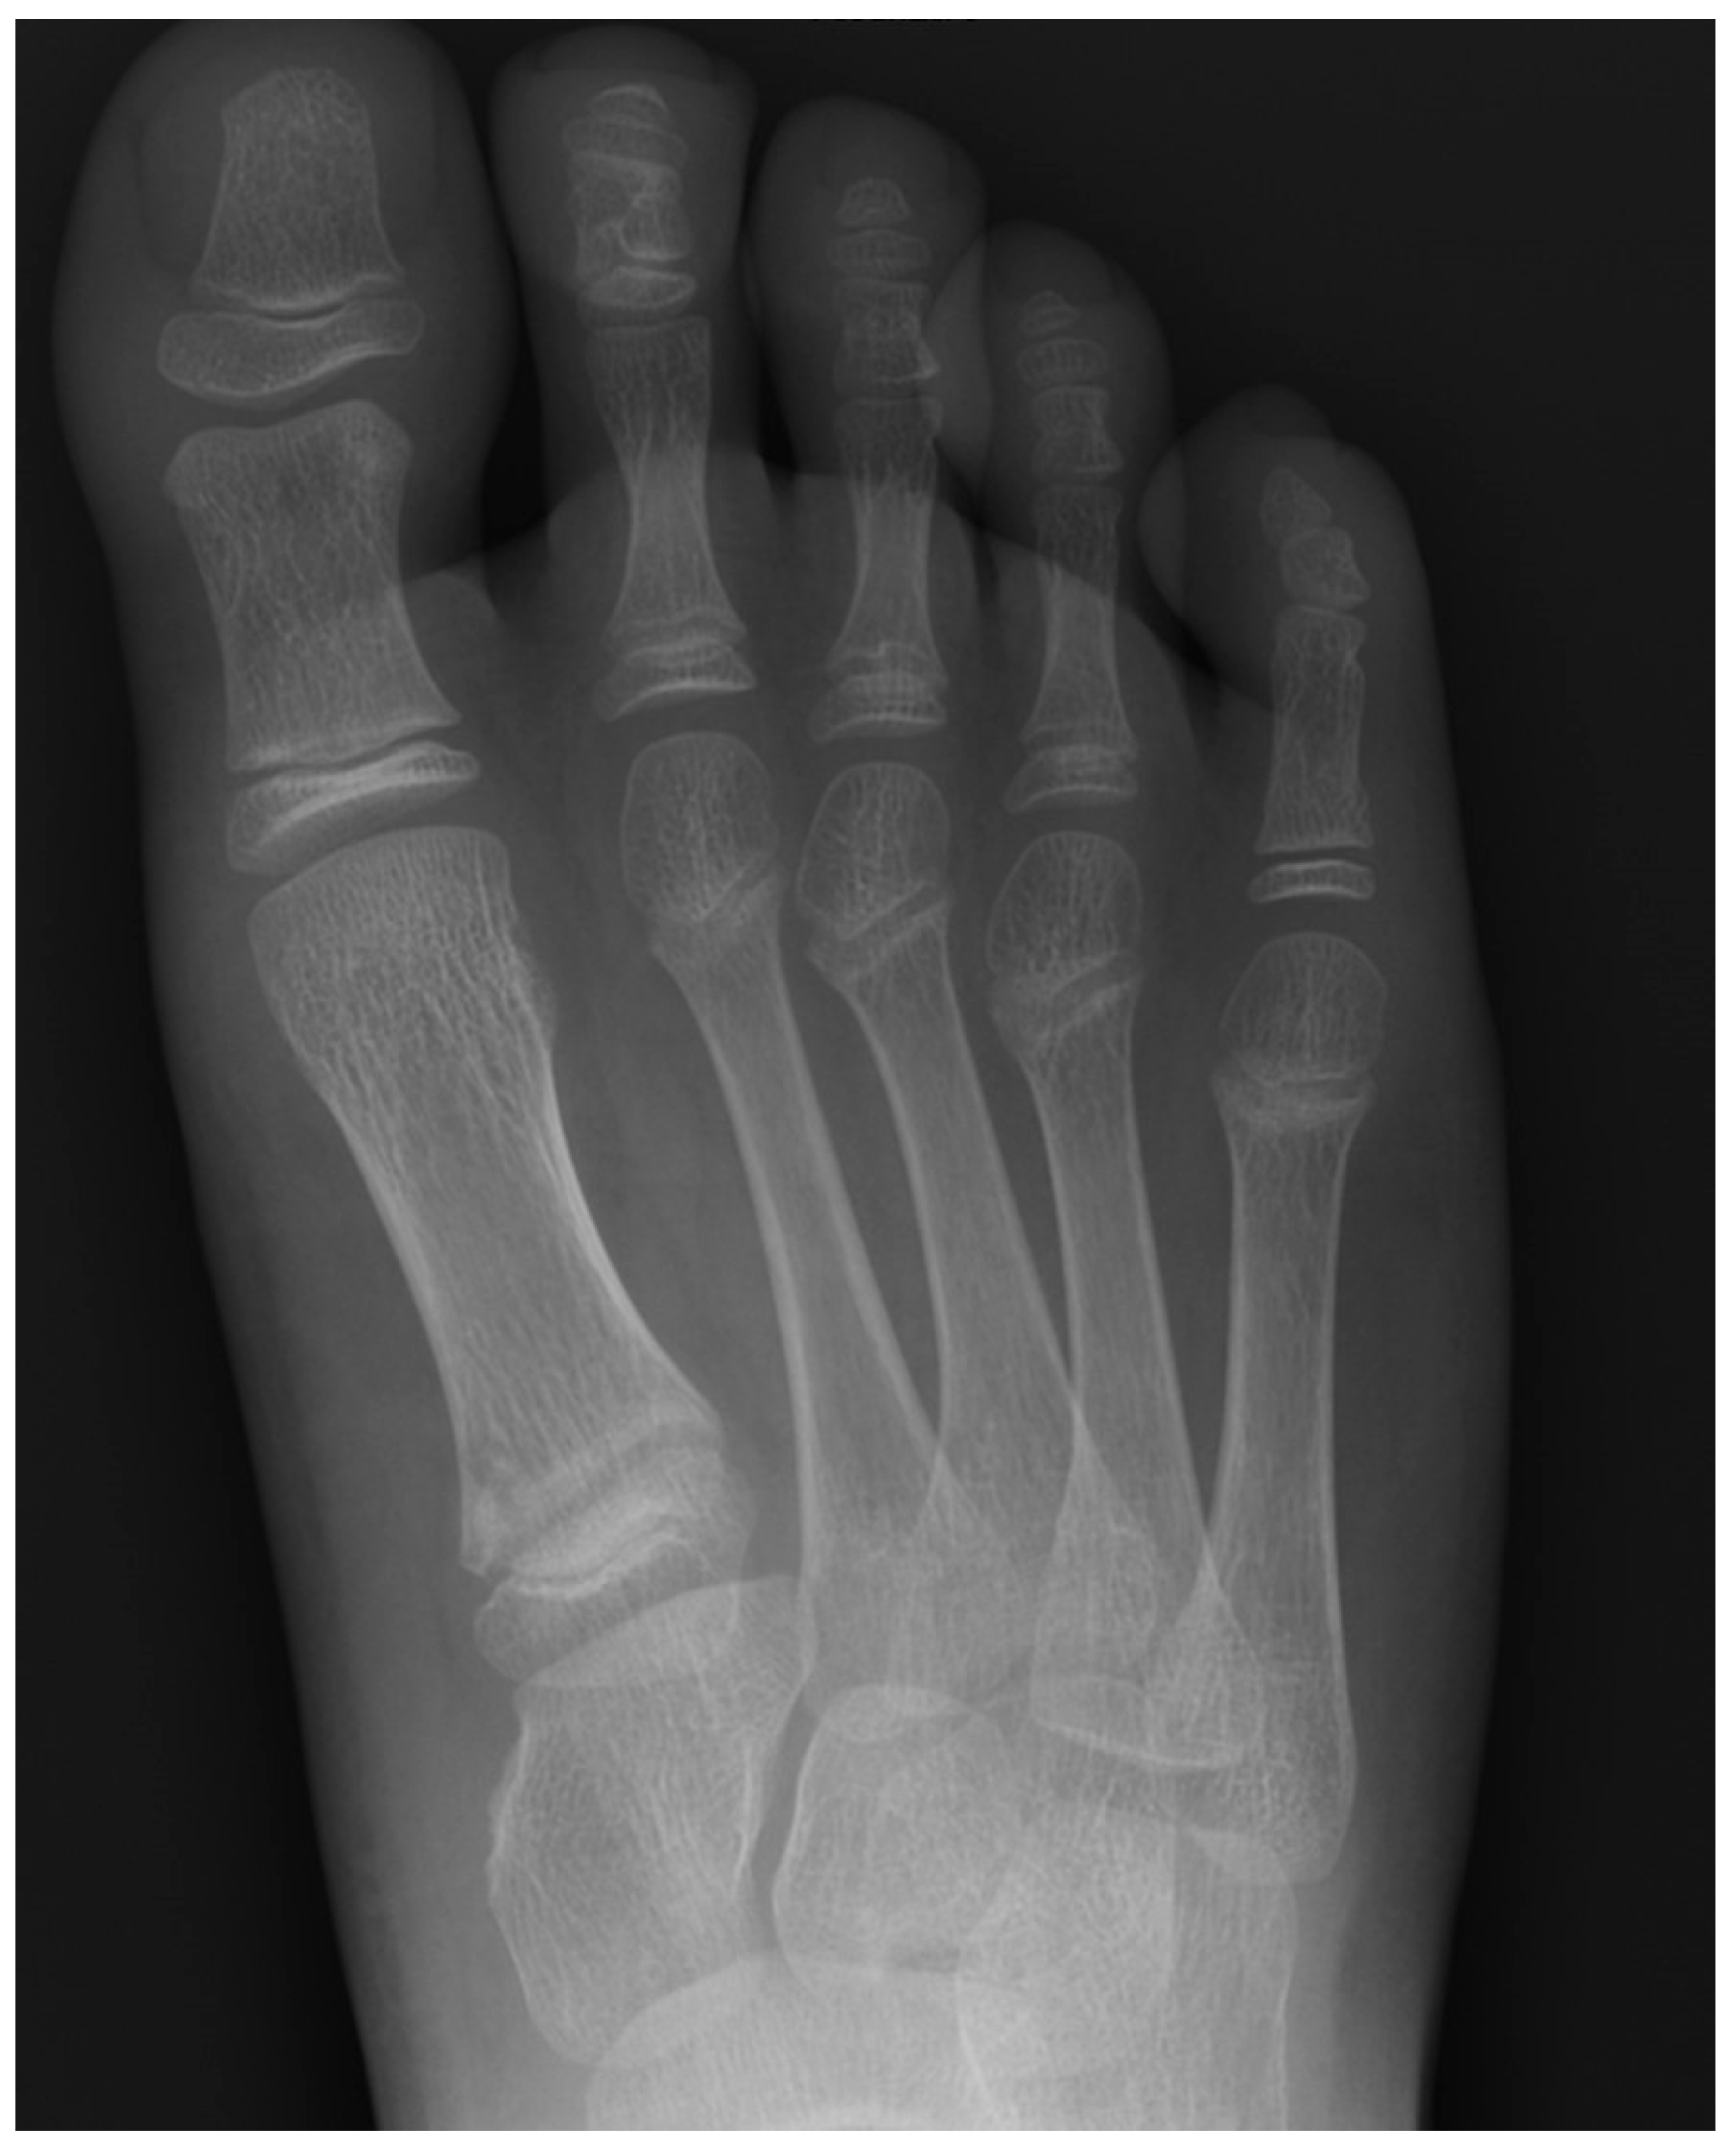

Plain radiographs are the cornerstone of imaging in the diagnosis of lesser metatarsal osteochondrosis. In the early stages of the disease, when supported by a suggestive clinical presentation, obtaining a comparative radiograph of the contralateral foot can be a useful diagnostic tool (Figure 9).

Figure 9.

Radiograph of a symptomatic 10-year-old female patient showing early sclerosis and flattening of the second metatarsal head on the left foot, compared to the contralateral side.

In the later stages, radiographs may reveal characteristic changes including subchondral sclerosis, fragmentation, and flattening of the affected metatarsal head (Figure 10 and Figure 11). In some cases, the presence of joint space narrowing or bony irregularities may also be observed. However, early changes, such as bone marrow edema or subtle cartilage damage, may not be visible on standard radiographs. MRI is particularly useful in the early stages of the disease, as it can detect bone marrow edema, which is a sign of active bone inflammation and necrosis, even before structural changes become apparent on radiographs (Figure 10, Figure 11 and Figure 12).